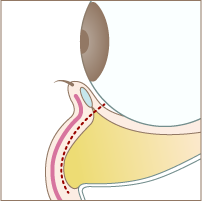

About裏ハムラ法

「裏ハムラ法」は、まぶたの裏側を切開して、脂肪を移動させる方法です。皮膚を切らないので、表面に傷跡を残さず治療が可能です。ただ『ハムラ法(目の下のたるみ取り)』と違い、皮膚のたるみを解消することは難しいので、症状によっては充分なたるみ改善効果を得られないことがあります。 当院では、一人ひとりの症状を見極め、「ハムラ法」「裏ハムラ法」のどちらが最適かをご提案しますので、たるみ症状や自身にぴったりの治療法が分からなくても、安心してご相談ください。

Treatment Step施術手順

Step 01

まぶたの裏側の赤い点線部分を切開します

Step 02

脂肪が溜まっている部分の下側の隔膜を切開します。

Step 03

隔膜と眼窩脂肪を一塊として引き下げ、骨膜に縫合します。

Step 04

切開した部分を縫合して完成です。